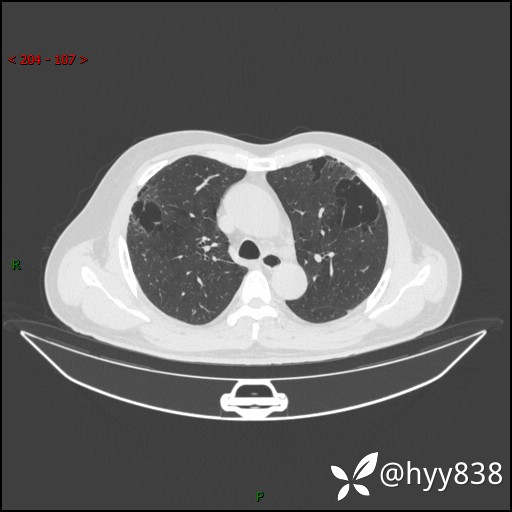

一周后胸部CT